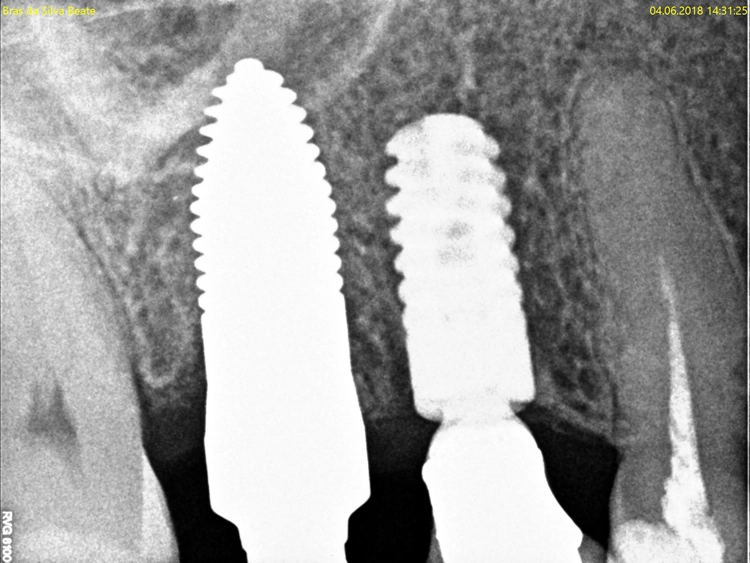

Nach der ersten klinischen Befundaufnahme und Fotodokumentation der Ausgangssituation (Abb. 1) wurde zur Ergänzung des klinischen Befundes eine Einzelzahnaufnahme erstellt (Abb. 2). Vom Oberkiefer wurde eine Abformung genommen, um eine Tiefziehschiene herzustellen. Diese wird direkt am OP-Tag genutzt, um eine provisorische Krone herzustellen.

Aufgrund der traumatischen Extraktion des ankylosierten Zahnes, die zu einer Osteotomie wurde (Abb. 3), fehlten die vestibuläre und palatinale Lamelle (Röntgenkontrollbild während der Osteotomie, Wurzelrest noch vorhanden Abb. 4). Dieser Wurzelrest wurde entfernt. Bei dem geringen Restknochenvolumen war eine Sofortimplantation nicht mehr indiziert.

Kontrollbild und Röntgenkontrolle ein Jahr und ein Monat nach Socket/Ridge Preservation (Abb. 21 und 22). Der komplette Umbau zu Eigenknochen ist noch nicht abgeschlossen. Die Papillenregeneration zwischen 13/14 und 14/15 ist jedoch deutlich erkennbar.